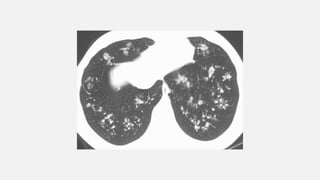

Diffuse Patchy Consolidation •seen with any pneumonia (bacterial, mycobacterial, fungal, viral, PCP), • pulmonary edema (hydrostatic and permeability), • acute respiratory distress syndrome (ARDS), • pulmonary hemorrhage • aspiration, • inhalational diseases • eosinophilic diseases • invasive mucinous adenocarcinoma. .

• #31  Diffuse patchy consolidation in a patient with viral pneumonia.